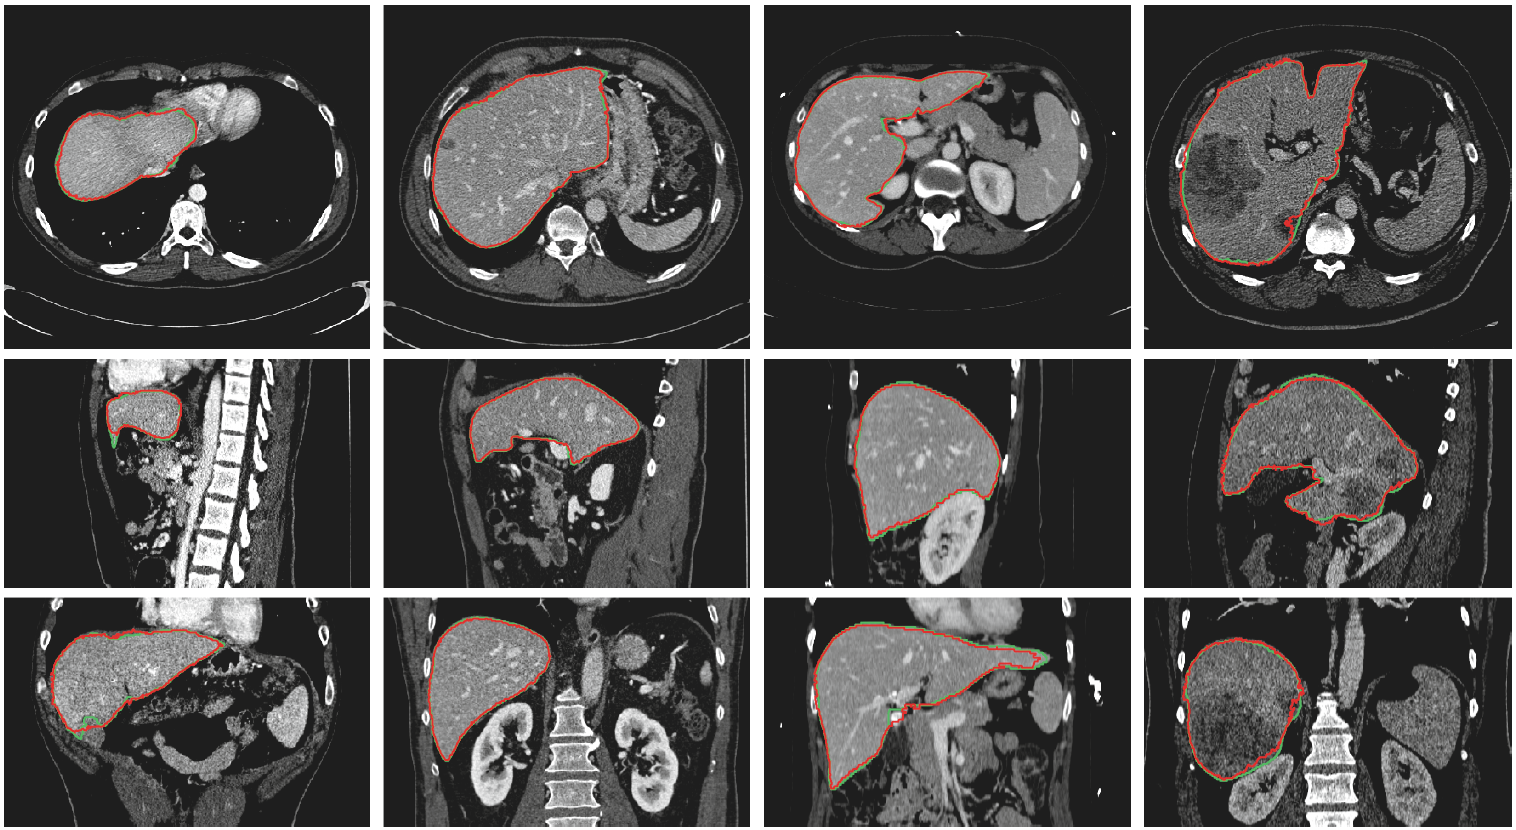

3D Deeply Supervised Network for Automatic Liver Segmentation from CT Volumes

Qi Dou, Hao Chen, Yueming Jin, Lequan Yu, Jing Qin, Pheng-Ann Heng.

Medical Image Computing and Computer Assisted Intervention (MICCAI), 2016.

(Young Scientist Award Finalist)